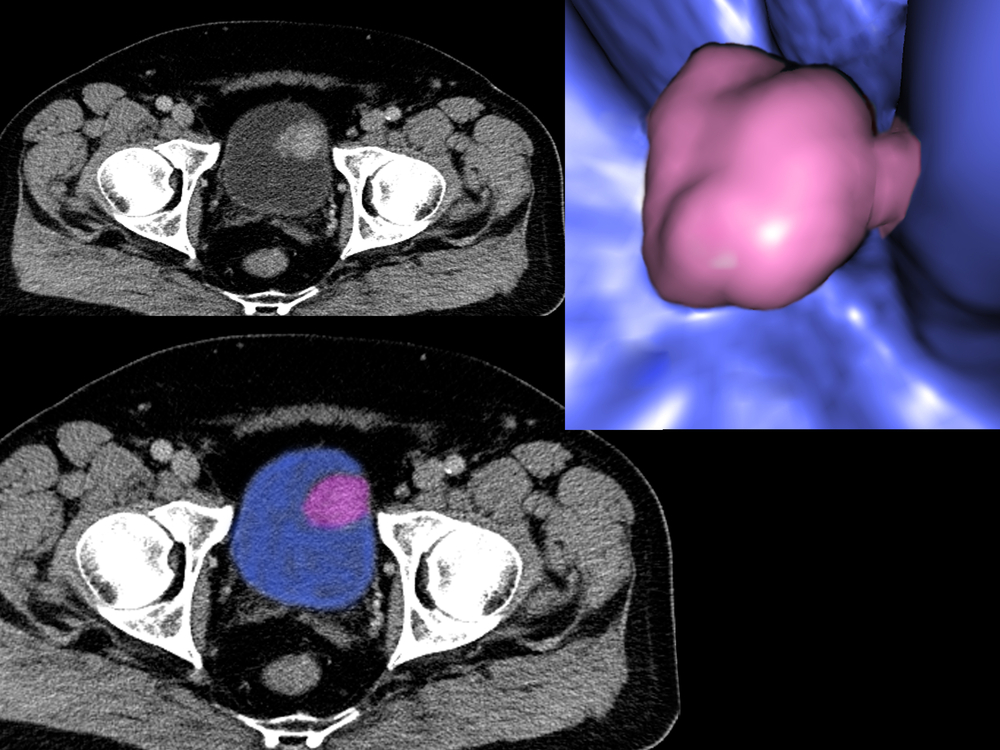

- рентгенодиагностические методы: выделительная урография, цистография, ангиография, компьютерная томография. Помогают оценить распространенность опухоли;

- магнитно-резонансная томография, снижающая лучевую нагрузку на больного и позволяющая построить трехмерную модель опухоли.